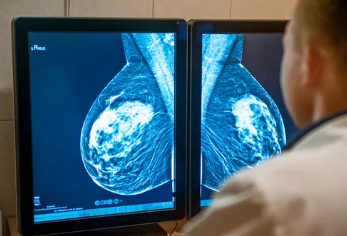

**유방촬영(맘모그라피, Mammography)**은 유방암을 조기에 발견할 수 있는 가장 기본적인 검사 중 하나입니다.

유방촬영술은 유방 내 조직 변화를 엑스레이를 통해 관찰하는 검사로,

- 유방암을 조기에 발견하기 위한 목적

- 혹, 석회화, 종괴, 조직 밀도 등을 확인